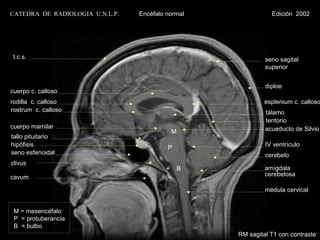

CATEDRA DE RADIOLOGIA U.N.L.P.   Encéfalo normal              Edición 2002

t.c.s.                                                      seno sagital

superior

diploe

cuerpo c. calloso

rodilla c. calloso                                          esplenium c. calloso

rostrum c. calloso                                          tálamo

tentorio

cuerpo mamilar                                              acueducto de Silvio

M

tallo pituitario

hipófisis                                 P                 IV ventrículo

seno esfenoidal                                             cerebelo

clivus

B            amígdala

cavum                                                       cerebelosa

médula cervical

M = mesencéfalo

P = protuberancia

B = bulbo

RM sagital T1 con contraste